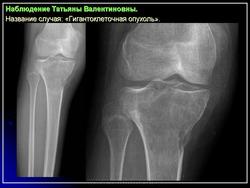

Гигантоклеточная опухоль.

1.gko_.slayd22.jpg2.gko_.slayd23.jpg